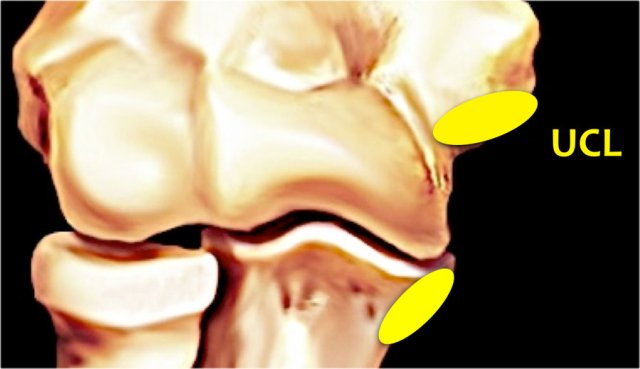

Ulnar collateral ligament or UCL

Starts at the undersurface of the medial epicondyle and runs down to the sublime tubercle, which is the medial side of the coronoid process.

The ulnar collateral ligament (UCL) is situated on the medial side and it has three components.

The anterior bundle is the strongest component and is the primary restraint against valgus forces.

On MR this is the most important structure.

The posterior bundle attaches distally in a fan-shape on the olecranon.

It forms the floor of the cubital tunnel.

The transverse bundle runs from the olecranon to the olecranon, so it doesn't do much.

The UCL (in yellow) originates on the undersurface of the medial epicondyle just beneath the origin of the common flexor tendon.

It attaches on a small process on the medial side of the coronoid, which is called the sublime tubercle.